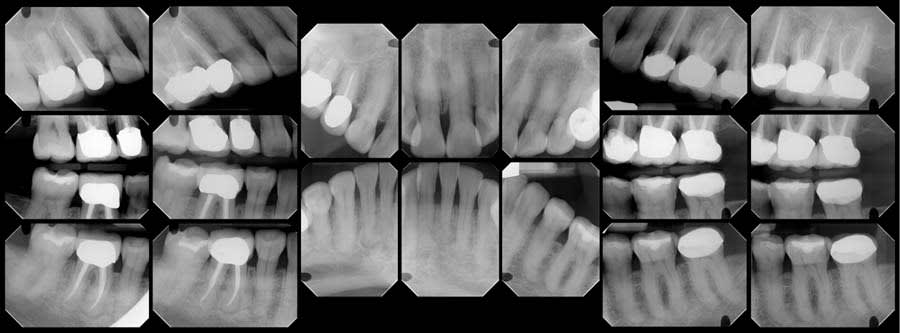

To establish a differential diagnosis, in addition to testing both teeth Nos. 29 and 30 for endodontic/periodontal disease, the clinician reviewed the patient’s systemic health and referenced a previous FMX captured in 2018, which demonstrated a progression of cementum deposition (Figure 2, left). Cementum deposition progression to concrescence of Nos. 25/26 could also be noted (Figure 3).

A review of the patient’s dental history revealed that she was never diagnosed with periodontitis, and bone loss had been attributed to physiological aging, gingival recession, and increased biomechanical loading. Tooth No. 19 had been extracted due to secondary caries and not periodontal conditions. The 2018 FMX exhibited generalized hypercementosis, including the mandibular right, mandibular central, and maxillary left posterior areas, and no evidence of concrescence (Figure 4). In 2022, the patient had a cone-beam computed tomography (CBCT) scan in preparation of the No. 19 implant where hypercementosis with concrescence could be seen with Nos. 25/26 and 29/30 (Figure 5).